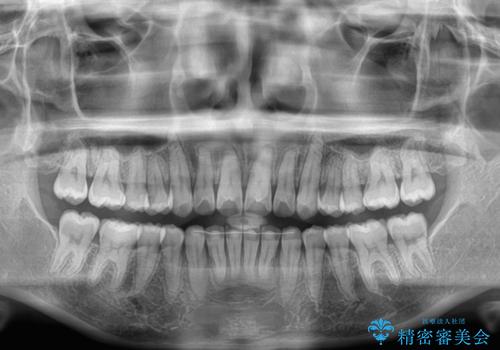

- 上の前歯の隙間を気にして来院された患者様です。

インビザラインにより、上下の歯列を側方に拡大しつつ、前歯の隙間を閉じていくこととしました。

隙間の原因は強い咬合力や舌の突出癖、小帯の異常付着などがありますが、舌のトレーニングをしっかりと行いながら、装着時間を遵守して装着していただいたおかげで、スムーズに治療を終えることができました。